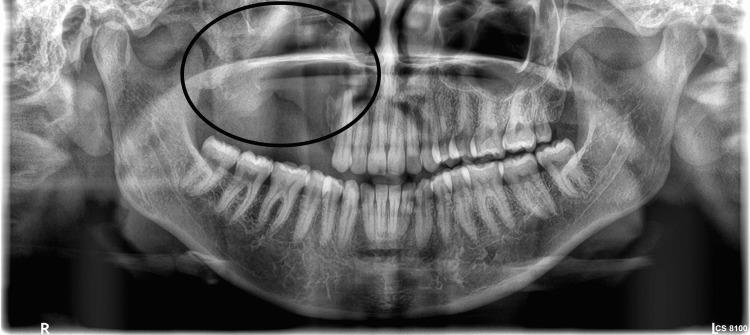

Odontogenic fibromyxoma typically presents as painless swelling in the jaw, and clinically, it grows slowly, becoming benign and asymptomatic. It causes the cortical plates to expand gradually, which leads to mobility and drifting of the teeth. Root resorption is also common. The tumor is locally aggressive in nature. It is also known to have a high recurrence rate. We present the case of a 30-year-old female patient who was diagnosed and treated for odontogenic fibromyxoma of the maxilla conservatively with enucleation. The radiograph showed a multilocular lesion, which can be confused with ameloblastoma, aneurysmal bone cyst, or odontogenic keratocyst. Hence, with proper clinical, radiographic, and histopathological examination, a correct diagnosis can be made and adequate treatment can be planned.

牙源性纤维黏液瘤通常表现为颌骨无痛性肿胀,临床上生长缓慢,呈良性且无症状。它导致皮质骨板逐渐扩张,进而引起牙齿松动和移位。牙根吸收也很常见。该肿瘤本质上具有局部侵袭性,且已知复发率高。我们报告一例30岁女性患者,她被诊断为上颌骨牙源性纤维黏液瘤,并通过摘除术进行了保守治疗。X线片显示为多房性病变,可能与成釉细胞瘤、动脉瘤样骨囊肿或牙源性角化囊肿相混淆。因此,通过适当的临床、影像学和组织病理学检查,可以做出正确诊断并制定适当的治疗方案。